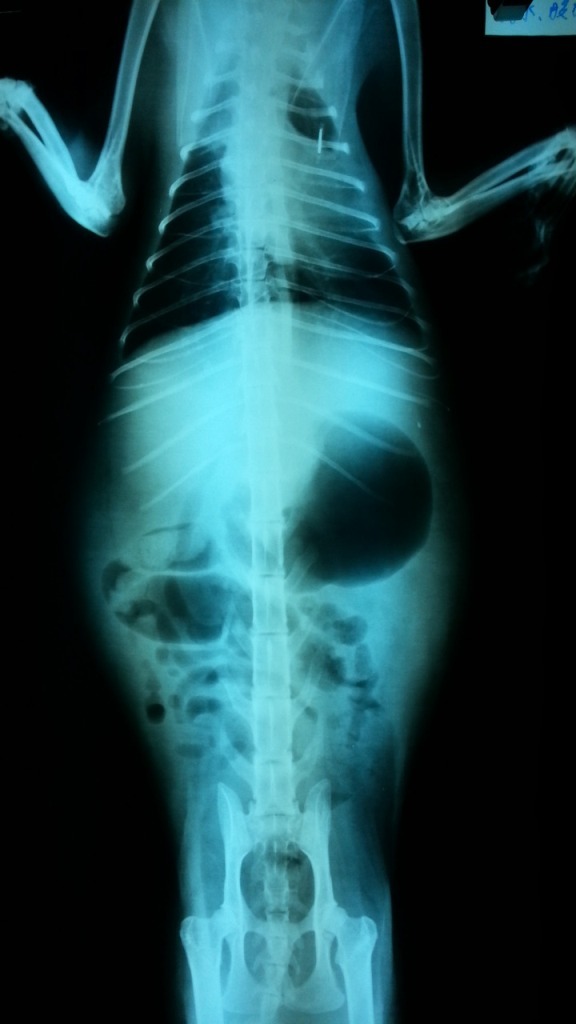

主題: 被丟棄在張媽媽門口的貓--腹水 申請者姓名: 張慧敏 花色: 申請日期: 2012-10-25 11:00:44 申請者部落格: 申請者臉書網址: 所在縣市/合作醫院: 台北市/澄毅動物醫院 治療費用: 6900元 需求人數: 16人 已結案 (2013-06-27 13:57:51) 報名人員: Winnie Chou(已付款)、Kay Liu(已付款)、Wei-rong Chen(已付款)、土司胖胖(已付款)、Denbe Yangchen(已付款)、ㄚ芳(已付款)、HI HI Little(已付款)、May Chuang(已付款)、Edwin(已付款)、李孟儒(已付款)、小羽(已付款)、小羽(已付款)、小羽(已付款)、小羽(已付款)、小羽(已付款)、小羽(已付款)、 候補人員: Bella、 動物病情說明: 這貓咪是連同奶貓被丟在張媽媽的場子門口

小貓離乳後,將這母貓帶到醫院節育後準備放回去,肚皮一直沒有消下去,後來食欲越來越不好,送到醫院檢查,發現肚子有腹水 三合一檢查陰性,抽腹水作蛋白質沉澱試驗及比重檢察高度懷疑是FIP

治療4天後往生